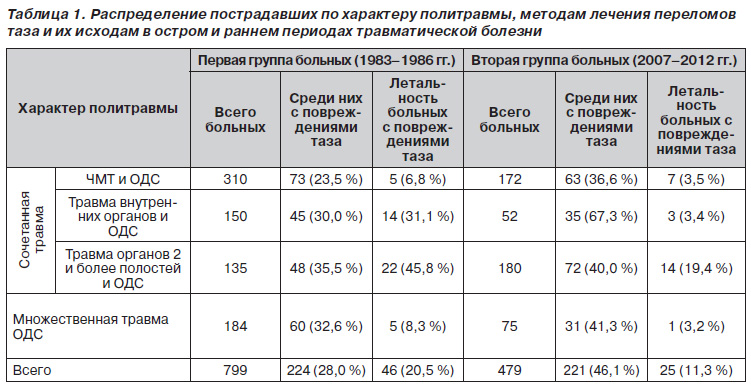

Изучены архивные материалы 1278 больных с политравмой, которые в остром и раннем периодах травматической болезни (ТБ) находились на лечении в отделении интенсивной терапии нашего учреждения. Из них у 445 (34,8 %) имела место множественная и сочетанная травма таза. Об эффективности лечения больных с повреждениями таза судили по снижению числа летальных исходов. При этом в зависимости от методов лечения переломов таза всех больных разделили на две группы.

В первую группу вошли 799 пострадавших с политравмой, лечившихся в 1983–1986 годах, из них 224 (28,0 %) имели повреждения костей таза. У больных с повреждениями таза в остром и раннем периодах травматической болезни основное внимание уделялось нормализации витальных функций. Для стабилизации переломов костей таза у этих пострадавших были применены консервативные методы (укладка по Волковичу, гамак, скелетное вытяжение, шины различных конструкций).

Во вторую группу вошли 479 пострадавших с политравмой, находившихся на лечении в период с 2007 по 2012 год, из них у 221 (46,1 %) были повреждения костей таза. В этой группе наблюдений у больных с повреждениями таза была применена разработанная нами медицинская технология лечения больных с политравмой, вобравшая в себя результаты научноисследовательских работ (НИР), выполненных в нашем институте, которыми доказано, что:

Распределение пострадавших по характеру политравмы, методам лечения переломов таза и их исходам в остром и раннем периодах травматической болезни представлено в табл. 1. Тяжесть травмы, согласно шкале ISS, в обеих группах больных составила от 18 до 59 баллов. Полученные данные свидетельствуют о том, что за последние 25 лет в структуре политравмы на 18,1 % (р < 0,001) увеличилось доминирование повреждений таза. В то же время, несмотря на возросшее число потерпевших с множественными и сочетанными повреждениями таза, летальность во второй группе снизилась на 9,2 % (р < 0,01), особенно при сочетанной травме органов двух и более полостей и опорнодвигательной системы (ОДС) — на 26,4 % (р < 0,001), а также при сочетанной травме внутренних органов и ОДС — на 27,7 % (р < 0,05). Показатели летальности при сочетанной черепномозговой травме (ЧМТ) и ОДС, а также при множественной травме ОДС достоверно не отличались (р > 0,05). Чем можно объяснить такой эффект? Прежде всего изменением стратегии и тактики лечения этой категории пострадавших. В первой группе при оказании помощи пострадавшим с тяжелыми повреждениями таза основное внимание уделялось восполнению кровопотери, вызванной длительным и массивным кровотечением. Кровопотеря восполнялась преимущественно кровью по принципу «капля за каплю».